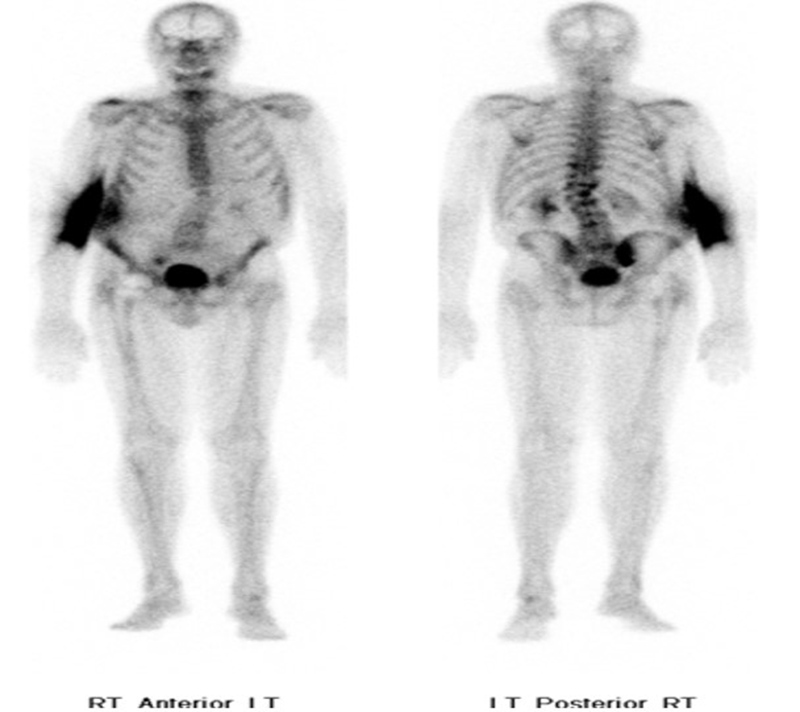

Focal bone marrow uptake may simulate bone infection, especially if it is an unusual location or situated next to an orthopedic prosthesis that could have associated loosening or infection (figure 32). Heterotopic bone formation (also called myositis ossificans) is fairly common after muscle injury or surgery of the extremities and joints. It can be seen in both the upper and lower extremities. It is particularly common in the elbow and hip after surgery or immobilization. It may be quite prominent and bizarre in its early stage and can be confused with malignancy if one is not careful. It is most easily recognized on hip, femur, or pelvis radiographs but is often seen on other imaging studies (figure 33). It is a benign finding that usually needs no further evaluation or treatment.

60 year-old man with history of lung cancer and left hip arthroplasty suffered from stiffness in the left hip region. Axial CT, FDG PET, fused axial, and coronal PET-CT demonstrates increased uptake of FDG in heterotopic ossification in the musculature of the left thigh. |